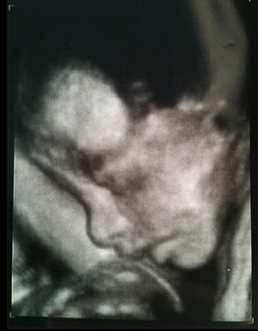

Wyman and I expect our baby boy Glenn Jolson at the end of September. His middle name is a reference to Al Jolson, the man who brought Wyman and me together. We have had some pregnancy issues over the past months, and we hope that Glenn Jolson will not make a too early appearance. His due date is September 29th, 2013.